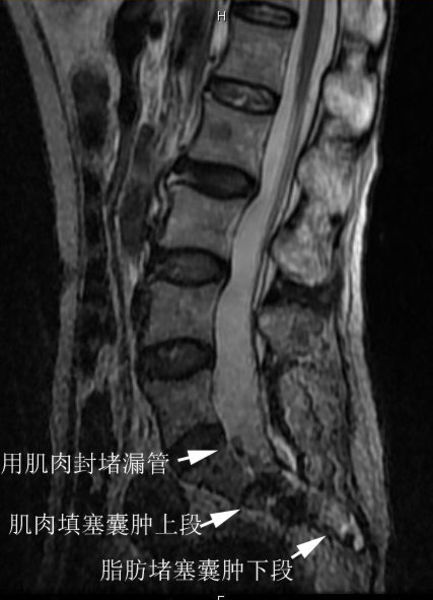

术后磁共振T2相显示,漏管已经被肌肉片从上向下的封堵成功,在此基础上,用肌肉(T2显示为灰黑色)填塞了囊肿的上段,用脂肪(T2显示为白色)填塞了囊肿的下段。囊肿内完全没有脑脊液了。